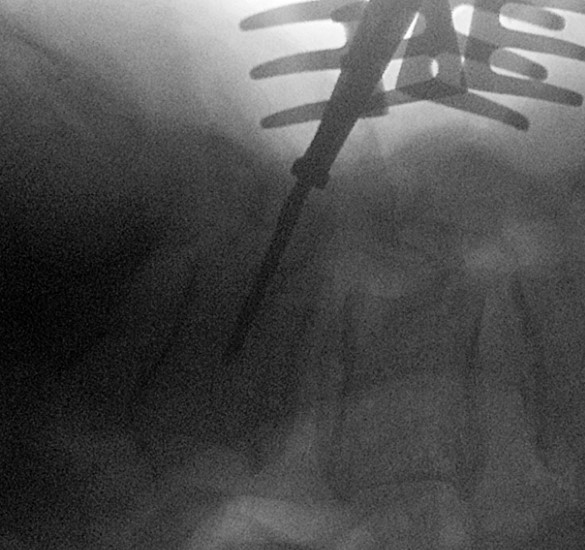

| placing-screw-in-L5.png | 2025-12-14 16:21 | 361K | ||